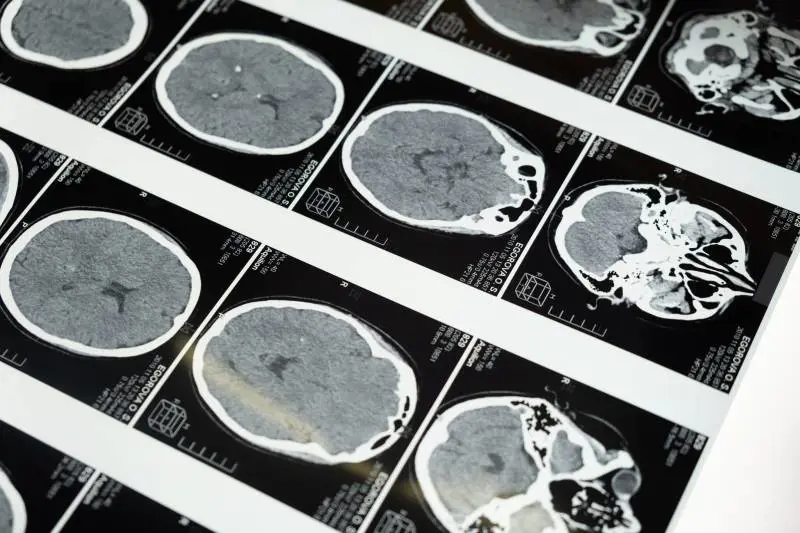

Dopo aver scoperto l'ospite indesiderato, si è subito proceduto all'estrazione del verme. Come riporta il The Guardian, la donna era stata ricoverata per la prima volta in quell'ospedale alla fine del mese di gennaio del 2021 a causa di settimane in cui soffriva di forti dolori all'addome ma aveva anche diarrea, febbre e tosse. L'anno successivo la 64enne ha sviluppato sintomi più gravi tra cui amnesie e depressione per le quali era stato necessario un altro ricovero: la risonanza magnetica aveva mostrato anomalie "ma il neurochirurgo certamente non è andato lì pensando che avrebbero trovato un verme che si dimenava", ha dichiarato al quotidiano inglese il dott. Sanjaya Senanayake, medico specializzato in malattie infettive dell'ospedale di Canberra. "I neurochirurghi si occupano regolarmente di infezioni nel cervello, ma questa è stata una scoperta che accade una volta nella carriera. Nessuno si aspettava di trovarlo".